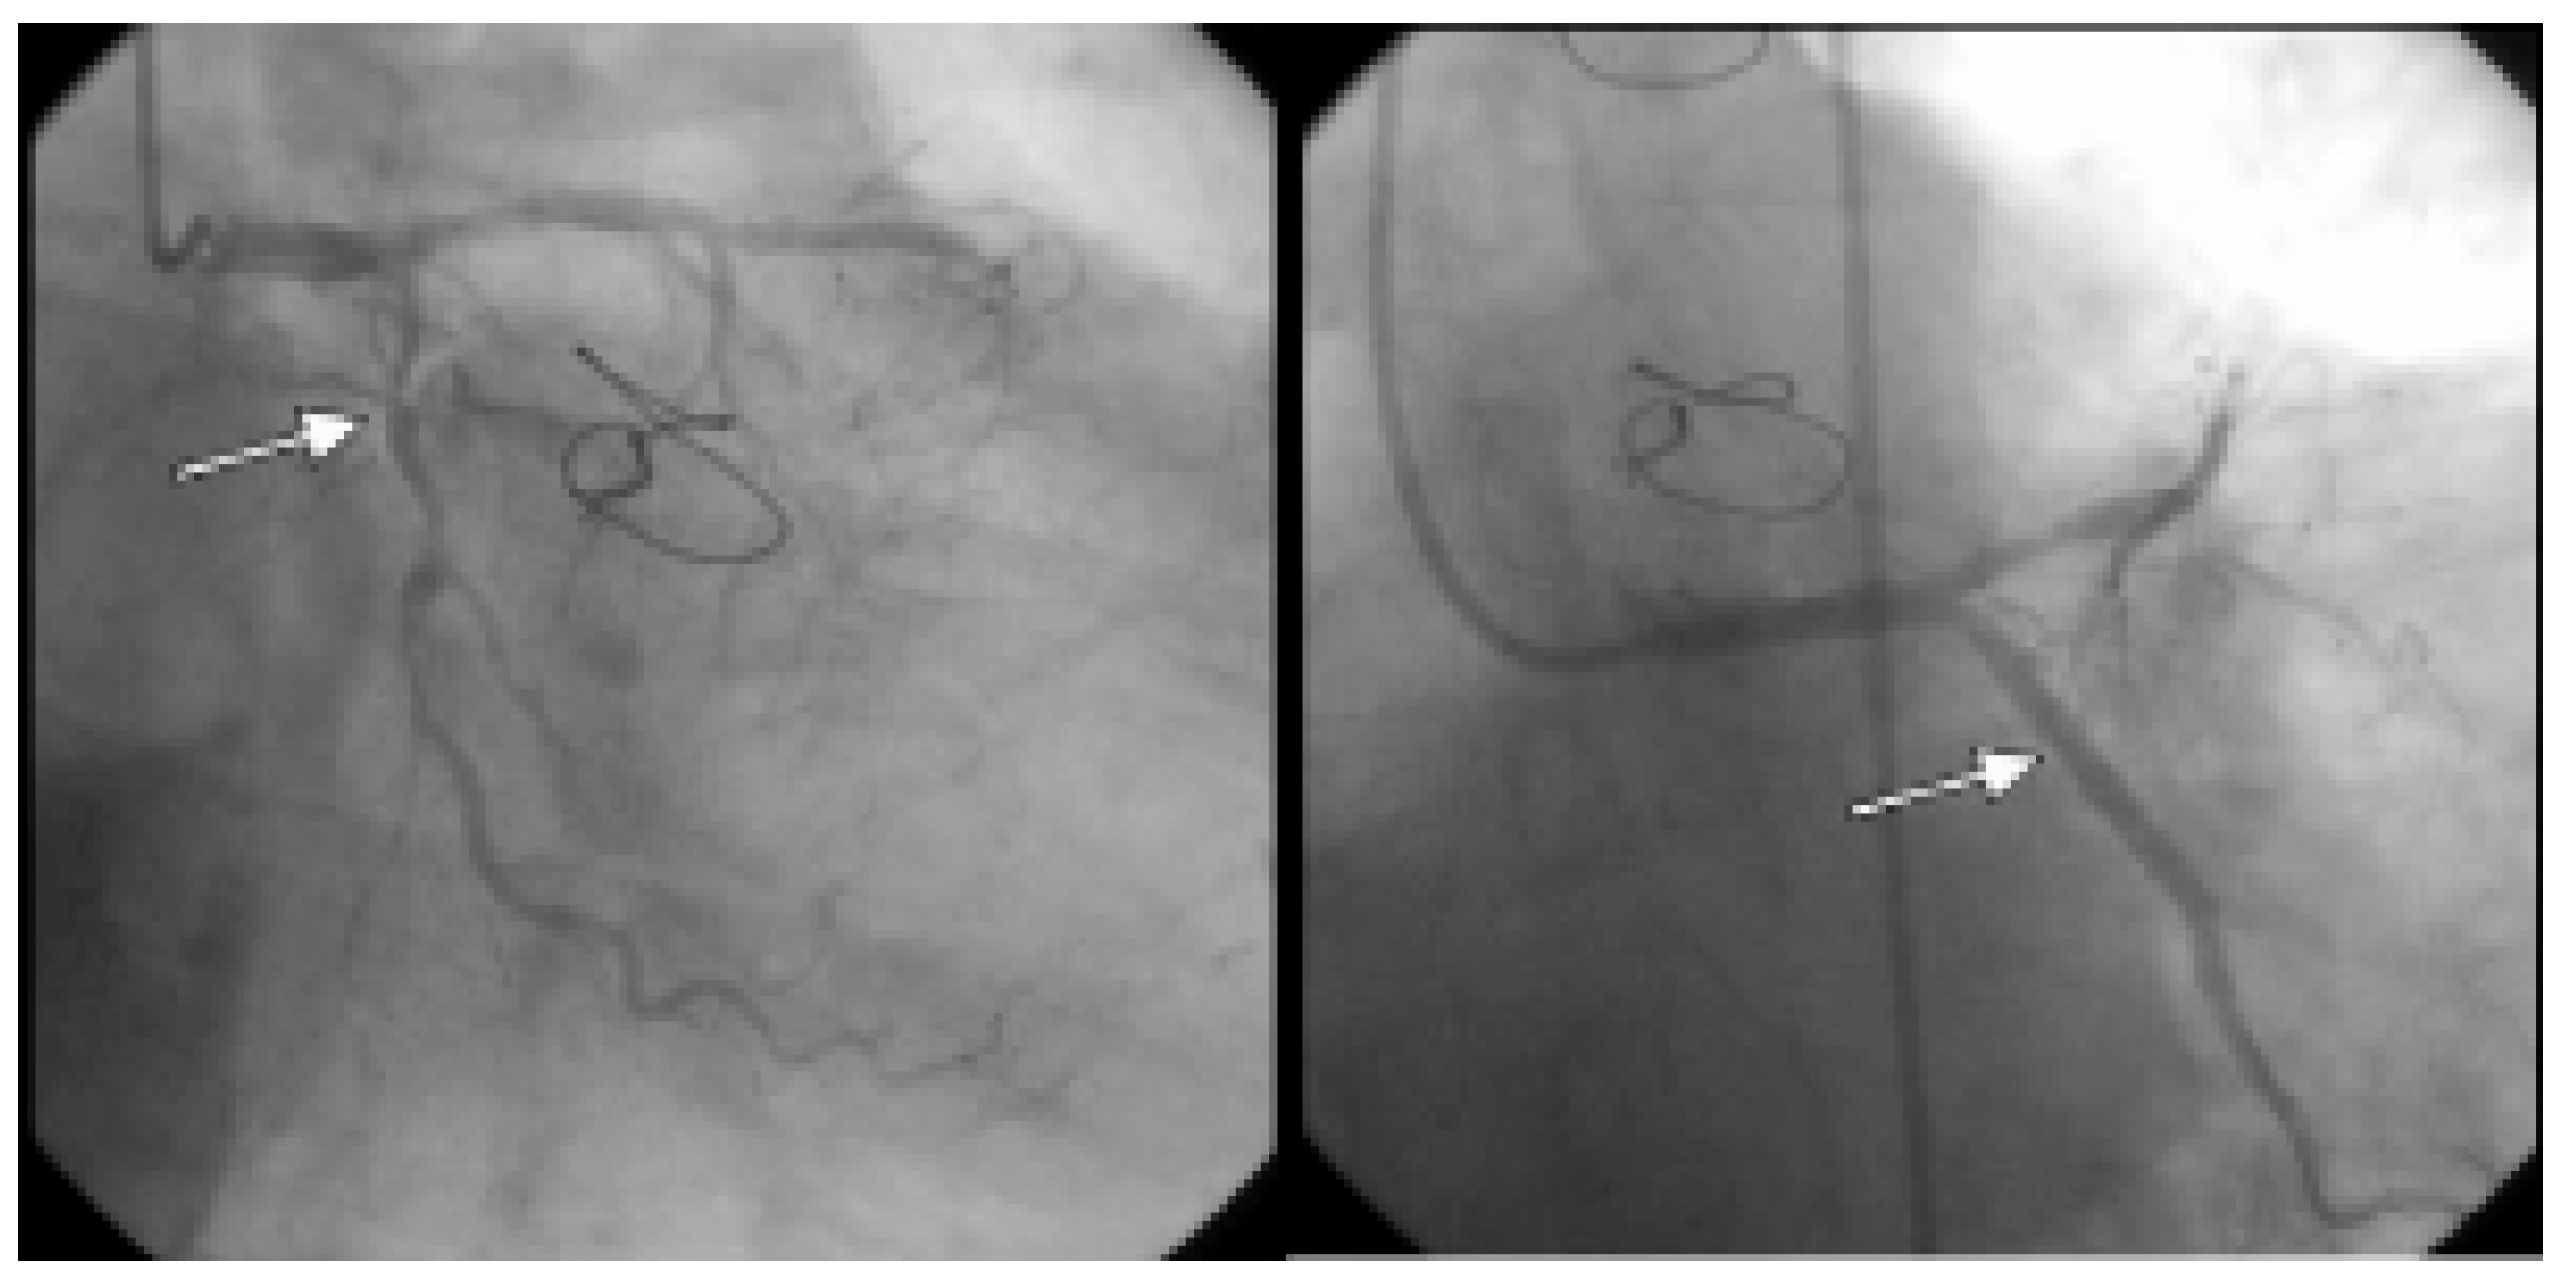

Nach Vorbehandlung mit Flüssigkeit und N-Acetylcystein fand sich koronarangiographisch als Hauptbefund eine subtotale komplexe mittlere RCX-Stenose, welche interventionell mittels mehrfacher Stent-Implantation behandelt wurde (Abbildung 1). Im Verlauf kam es zu einem CK-Anstieg bis max. 861 U/l bei einem RCX-Seitenastverschluss im Bereiche des gestenteten Segments. Nach anfänglich beschwerdefreiem Verlauf und Mobilisation des Patienten kam es in der Nacht nach dem Eingriff zu zunehmenden Thoraxschmerzen und Atemnot. Eine erneute notfallmässige Koronarangiographie wurde durchgeführt. Eine subakute Stent-Thrombose wurde ausgeschlossen, eine vorgängig belassene grenzwertig signifikante proximale RCX-Stenose wurde mittels Stent-Implantation versorgt. Insgesamt wurden innerhalb von 48 Stunden bei diesen zwei Koronarangiographien 550 mL (400 mL und 150 mL) Iopromid (Ultravist®)—ein nichtionisches niederosmolares jodiniertes Kontrastmittel—verabreicht. Im Laufe des nachfolgenden Tages entwickelte der stets hämodynamisch stabile Patient bei unveränderten Gewichtsverhältnissen und ausgeglichener Volumenbilanzierung klinisch-radiologisch ein Lungenödem mit Hämoptoe und transkutan gemessenen peripher-arteriellen O2-Sättigungen zwischen 70–80%. Daraufhin wurde der Patient maschinell beatmet, der Pulmonaliskatheter dokumentierte normale Druckverhältnisse (insbesondere normale pulmonal-kapilläre Verschlussdrücke) sowie einen normalen Cardiac Index (stets zwischen 4–5 l/min/m2). In der Bronchoskopie zeigte sich lediglich eine diffuse alveoläre Hämorrhagie. Laborchemisch imponierten u.a. erniedrigte Komplementwerte und eine temporäre Thrombozytopenie (minimal 98 × 103/μL). Eine Überwässerung wurde trotz steigenden Kreatinin-Werten bei ausgeglichener Bilanzierung und normalen Füllungsdrucken ausgeschlossen. Aufgrund dieser Befunde wurde ein nichtkardiogenes Lungenödem bei erhöhter Permeabilität der Lungenkapillaren nach Kontrastmittelexposition im Sinne eines ARDS diagnostiziert. Ein sekundärer pulmonaler Infekt wurde antibiotisch behandelt. Zudem kam es zu einem Nierenversagen (acute on chronic, kontrastmittelbedingt), welches mit temporärer veno-venöser Hämodiafiltration behandelt werden musste (Abbildung 2). Im weiteren Verlauf erholte sich der Patient zusehends und er konnte schlussendlich beschwerdefrei nach Hause entlassen werden.

Abbildung 1. Koronarangiographisch fand sich als Hauptbefund eine subtotale komplexe mittlere RCX-Stenose, welche interventionell mittels mehrfacher Stent-Implantation behandelt wurde. Im Bild links sieht man den präinterventionellen Befund, rechts postinterventionell.